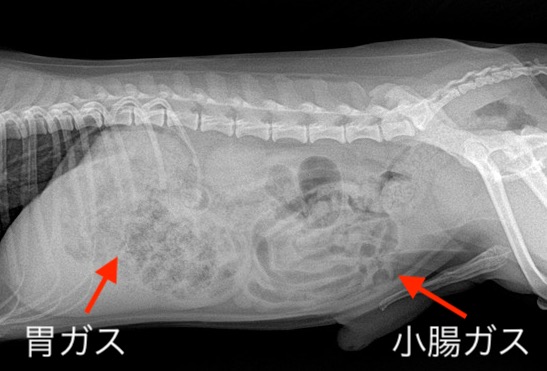

3歳、トイ・プードルの子になります。幼少期より嘔吐、下痢が認められています。

内視鏡検査にて、『リンパ球形質細胞性胃腸炎(IBD)』の診断が出ていましたので、

ロイヤルカナン消化器サポート(低脂肪食)にて治療を開始しました。

『治療前』:胃、小腸ともにガス貯留が明瞭になります。